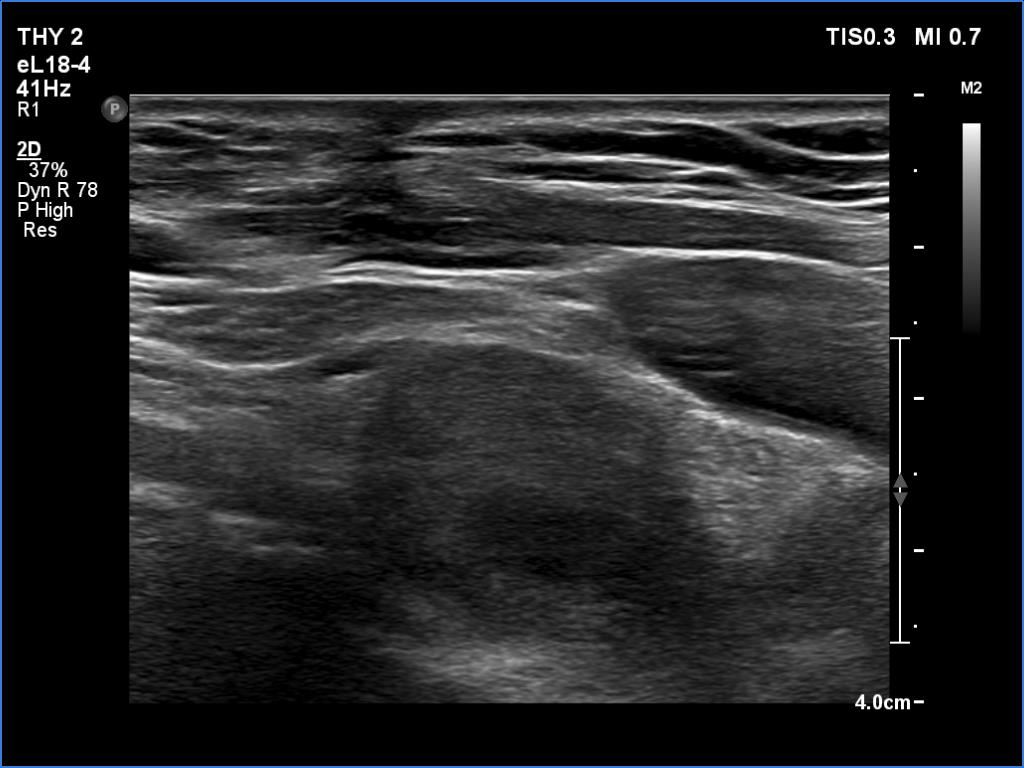

Second examination 6 month later (2nd row of images)

Ultrasonography revealed a hypoechoic mass corresponding to the right lower parathyroid.

The patient was reoperated and histopathology disclosed a parathyroid adenoma according to the right lower parathyroid.

If we compare the first and second ultrasound examination, it is evident that the ultrasound examination was not performed according to the rules of the profession at the first visit. (I will just mention that although in this case we only videotaped part of the entire study, we obviously overlooked the parathyroid gland under the right lobe. The reason for this is that we did not examine the part below the thyroid in the transverse section, and in the longitudinal section we started to examine the lower part of the thyroid too medially.)

Parathyroid surgery requires a lot of practice. The less experienced colleague who undertook the surgery judged that he would find a 1.5-centimeter lesion. But he also failed.